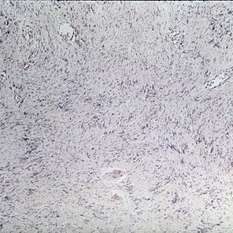

Benign reactive lymphoid hyperplasia, showing monotonous infiltrate of mature lymphocytes with occasional mitotic figure (H&E x252).

Condition/keywords: hyperplasia, lymphocytes